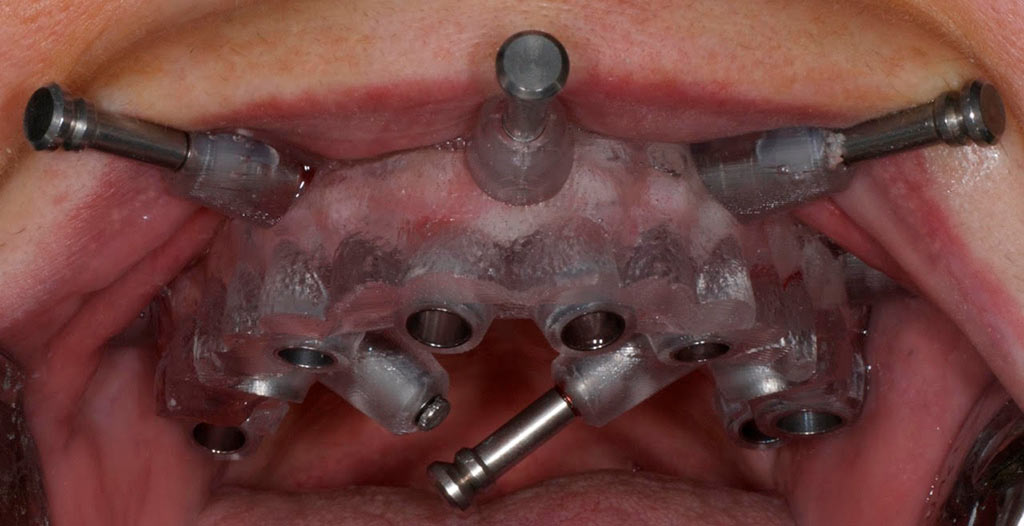

Completa inmediata,cirugía guiada, prótesis, puente de zirconio